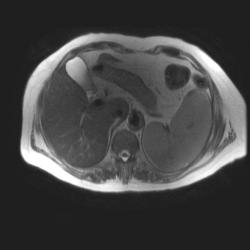

Женщина 47 лет, в течении долгого времени страдала от головных болей. В последние несколько месяцев - прогрессирующая потеря зрения (на оба глаза).

Presented images are corresponded for cerebral (right temporal-occipital region) neoplasia; high grade glioma is most suggested.

Глиальная опухоль.